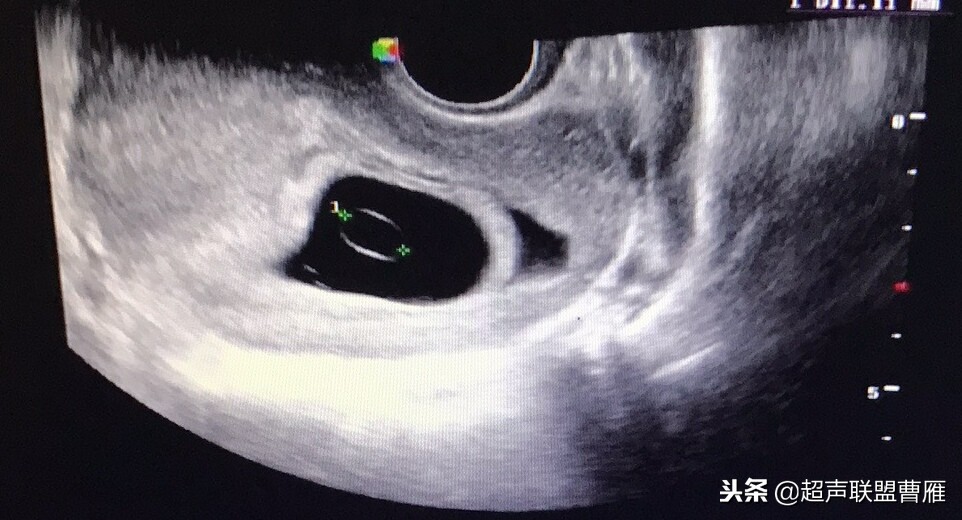

妊娠37天超声检查卵黄囊可以显示,羊膜腔及胚胎不能显示

真实的卵黄囊、胚体及羊膜腔形象

妊娠37天出现卵黄囊

在妊娠妊娠38天前后(36-40)天可以见到卵黄囊。 孕囊在6-9mm的可以见到其中有卵黄囊。

妊娠40天,见到卵黄囊、胚极及心管搏动, HCG12800U/L。

卵黄囊高分辨超声图像,妊娠40天